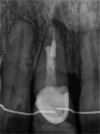

Introduction: Dental implants have become a standard treatment in the replacement of missing teeth. After tooth extraction and implant placement, resorption of buccal bundle bone can pose a significant complication with often very negative cosmetic impacts. Studies have shown that if the dental root remains in the alveolar process, bundle bone resorption is very minimal. However, to date, the deliberate retention of roots to preserve bone has not been routinely used in dental implantology.

Conclusion: Whilst the socket-shield technique potentially offers promising outcomes, reducing the need for invasive bone grafts around implants in the aesthetic zone, clinical data to support this is very limited. The limited data available is compromised by a lack of well-designed prospective randomised controlled studies. The existing case reports are of very limited scientific value. Retrospective studies exist in limited numbers but are of inconsistent design. At this stage, it is unclear whether the socket-shield technique will provide a stable long-time outcome.